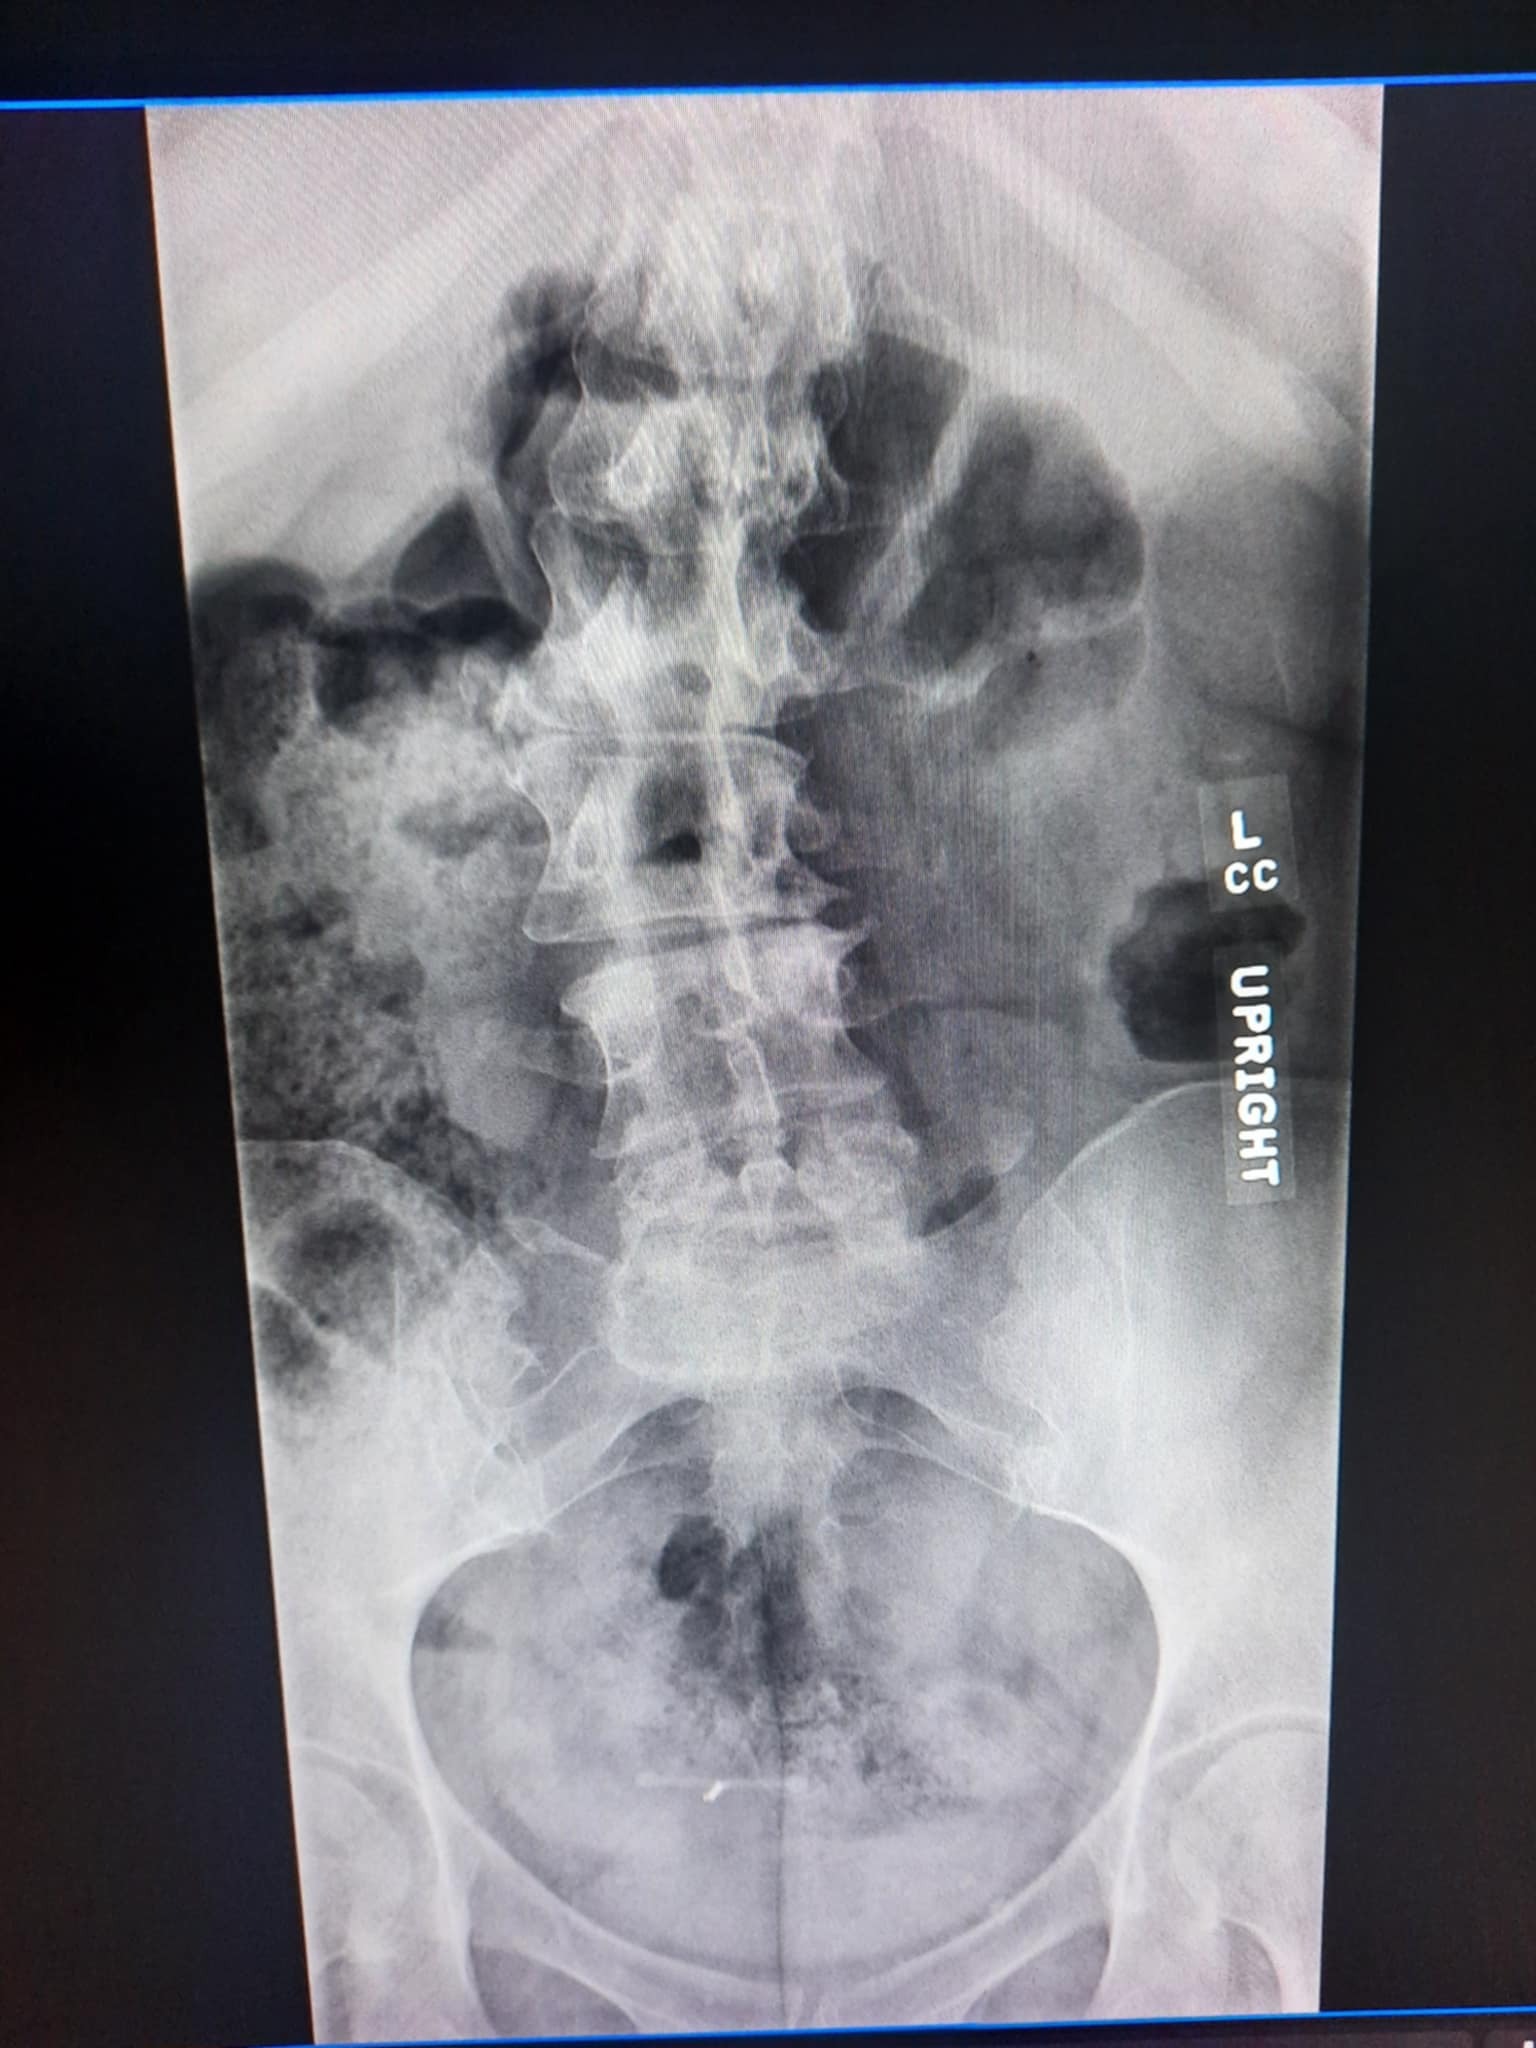

2/3/2026-XRay findings from 2/2/2026 Xray:

Findings/impression:

1. Right convex lumbar spinal curvature measuring 22 degrees.

2. Chronic L5 spondylolysis with stable mild anterolisthesis at L5-S1 which remains fixed between flexion and extension.

3. Mild fixed retrolisthesis at L3-L4 and L4-L5.

4. Stable multilevel disc degeneration, moderate in degree at L5-S1, and at least moderate multilevel facet hypertrophy.

Narrative

L SPINE W FLEX/EXTEND

Clinical Indication: Lumbar radiculopathy.

Comparison: External lumbar radiograph series 9/9/2025 and MRI 9/3/2025.

***New findings: "Mild fixed retrolisthesis at L3-L4 and L4-L5."

This means further progression since last fall. :(